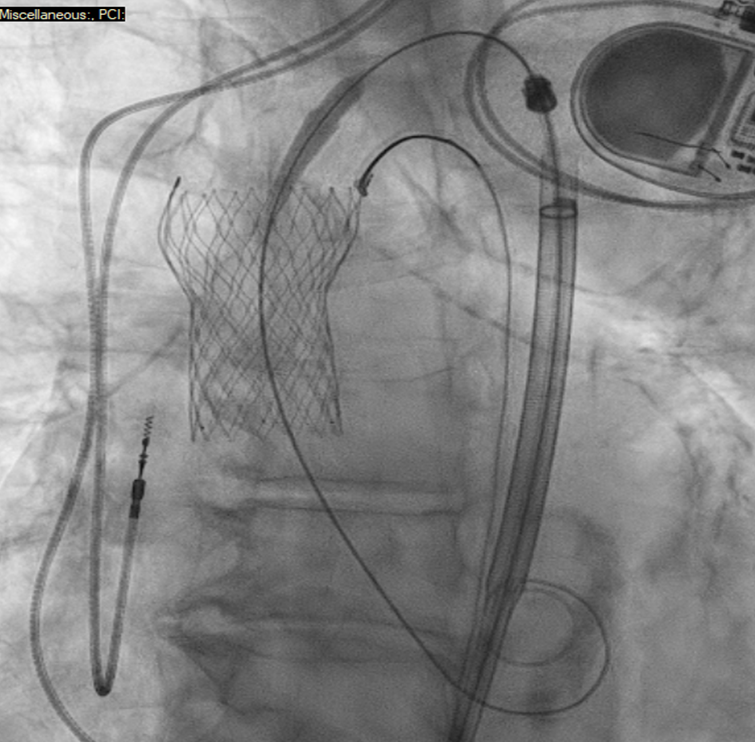

结合患者血流动力学稳定、移位瓣膜已被捕获固定、跨平台瓣膜输送的技术可行性等因素,治疗团队最终决定采用第三种方案:选择23mm Sapien 3 Ultra Resilia球囊扩张式瓣膜,实施跨平台“瓣中瓣”植入。

23 mm Sapien Ultra Resilia valve advanced through the frame of dislodged valve and positioned across the native annulus

23 mm Sapien Ultra Resilia 瓣膜系统经移位瓣膜栓塞瓣架内推进,跨原生瓣环定位

瓣膜尺寸选择:基于术前CTA测量的主动脉瓣环直径,结合移位瓣膜的瓣架内径,最终选择23mm Sapien 3 Ultra Resilia瓣膜——该尺寸既保证了通过性,又能在扩张后与原生瓣环形成良好贴合,减少瓣周漏。

输送与定位:在TEE与造影双引导下,将Sapien瓣膜输送系统沿导丝缓慢推进,通过移位的Evolut FX瓣膜瓣架,精准定位至原生主动脉瓣水平。过程中未遇到明显阻力。

瓣膜释放:通过快速心室起搏降低心输出量,减少瓣膜移位风险,随后启动球囊扩张,将Sapien瓣膜精准释放于目标位置。释放后即刻造影与TEE显示:瓣膜定位良好,无明显移位,瓣叶活动正常。